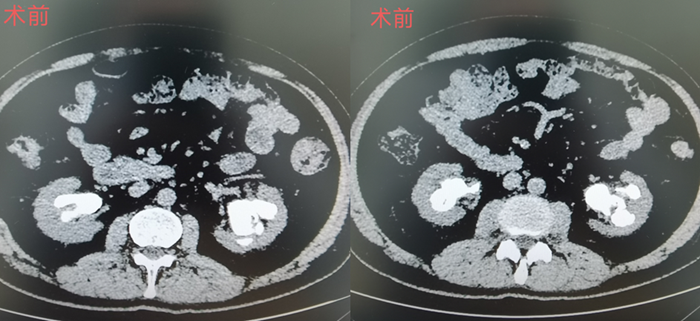

今年59岁的黄先生,来自湖北。半年来,他反复双侧腰部酸胀痛,有尿频尿急,而且每每小便时,都能看见尿液带血。黄先生在当地医院就诊行CT检查发现双肾巨大铸型结石,曾先后辗转于多家大型医院治疗未果,花费不少,使原本就不宽裕的家庭雪上加霜,黄先生满心沮丧。

通过围手术期凝血因子替代治疗、术中采取特殊体位,术前术后监测凝血因子等综合措施,在王金根、贾灵华两位主刀医师及麻醉科、手术室全体医护人员的努力下,先后双侧经皮肾镜取石术进展顺利,术后康复顺利,无明显出血、发热等并发症。术后复查腹部平片和CT提示结石彻底清除干净,术后患者血尿、腰疼等不适症状消失,黄先生带着灿烂的笑容出院。